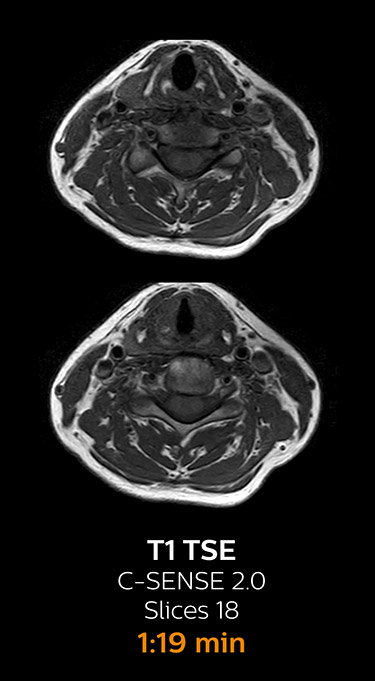

Fast MRI of cervical spine

With Compressed SENSE, the scan time for the routine cervical spine examination at KNC was reduced from 13:11 to 9:52 minutes, which corresponds to 25% reduction.

MRI examination of cervical spine with Compressed SENSE

MRI examination of the cervical spine with Compressed SENSE

Ingenia 3.0T CX

Scan time 9:52 min. (was 13:11 min. without Compressed SENSE)